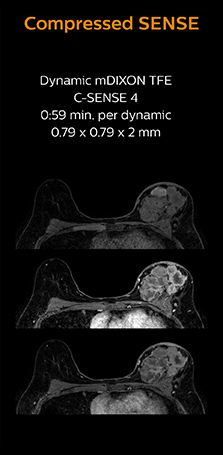

“In breast scanning, high resolution is important to help me identify very small mammary lesions, so, we need high spatial resolution in 2D T1- and T2-weighted images, as well as a short scan time. Compressed SENSE has allowed us to increase spatial resolution, which benefits our diagnostic confidence.”

Dr. Koyama says that he used to believe that high resolution MRI at 1.5T required long scan times, and SNR was low. “With Compressed SENSE, however, it is possible to acquire high quality images, even with higher Compressed SENSE factors, so in a quite short time.”

Dr. Koyama says that a C-SENSE factor of 4.0 was chosen to increase their spatial resolution in 3D dynamic breast scanning. “In addition to a high temporal resolution, we also require high spatial resolution, which helps us to see details of the internal structure of the lesion and to see lesions separately from normal anatomic structures. We can also see if a lesion extends into adjacent organs and anatomic structures.”

This patient underwent MRI on Ingenia 1.5T with Compressed SENSE. Compressed SENSE was used to reduce the scan time in order to decrease the time that the patient may experience discomfort and pain, both of which may lead to patient motion. The 3D BreastVIEW and 3D high resolution mDIXON images – both mDIXON contrasts are acquired in the same exam – show high quality images even with the shorter scan time. The spatial resolution of the dynamic scan with Compressed SENSE is higher than in the previous protocol (not shown) which allows for better visualization of the lesion with respect to the muscles of the thoracic wall and better delineation of small structures.

For breast imaging, a fast, high resolution scan can be important for a female patient having to lie in an uncomfortable, face-down position in the scanner. Compressed SENSE also helps us to obtain higher1 quality images using 3D BreastVIEW and 3D high resolution mDIXON sequences in the same examination time as in our previous exam protocol.